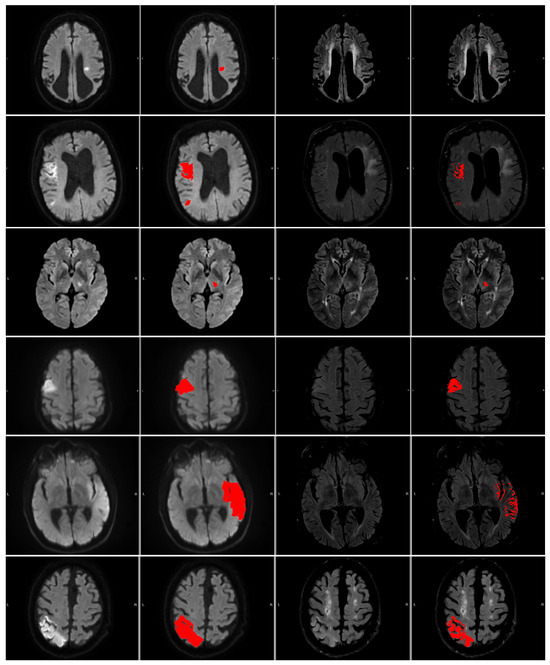

Figure 5. The numbered outlier cases from Figure 4. The cases are presented in ascending order 1 (top) through 6 (bottom). All cases are shown as (left to right) DWI (b1000), DWI (b1000) with segmentation (red area), FLAIR, and FLAIR with segmentation (red area).

The 6 numerated cases can be seen in Figure 5. Case 1 is a situation where both the area of interest and the contralateral side are slightly hyperintensive, leading to a small DWI/FLAIR mismatch ratio but large intensity measure and a no-mismatch assessment in the clinic. In Case 2, part of the contralateral side is hyperintense, which may lead to slight under-segmentation. However, the contralateral hyperintensity is not large enough to be clear from the intensity measure. Cases 3 and 4 correspond to two cases where the patients are deemed to be mismatch cases at the hospital, but our measures disagree. Case 5 shows a mismatch assessed case where the measures agree. Case 6 shows a no-mismatch assessed case where the measures and the assessment agree. Furthermore, the case shows the relevance of our criterion that the intensity be brighter than the mean plus 0.25 standard deviations, as part of the contralateral side is hypo-intense.